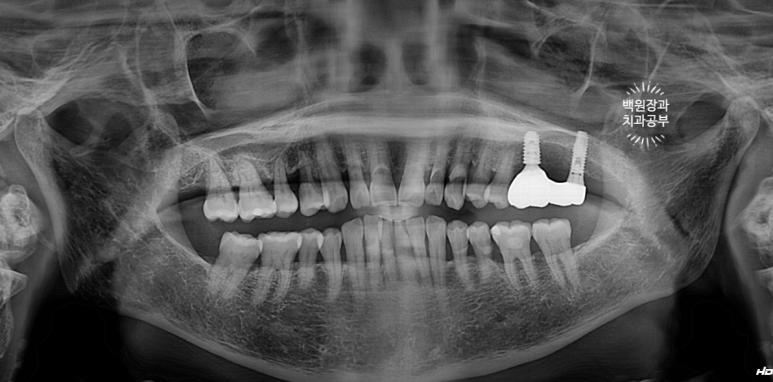

약 4개월이 지난 시점에서,

이식해두었던 뼈이식 재료와, 함께 재생된 새로운 잇몸뼈가 양질의 구성을 이루고 있음을 눈으로 직접 확인 후,

해당 부위에 임플란트를 새로 심어드렸어요.

오스템 TS BA 직경 5.0mm 길이 8.5mm 임플란트를 심어드렸는데,

딱 보시더라도 기존의 임플란트보다 훨씬 두꺼운 것을 보실 수 있을거에요.

큰어금니 부위는 임플란트가 하중을 많이 받기 때문에,

가능한한 두꺼운 임플란트를 심어드리는게 아~주 중요합니다.

얇은 임플란트를 심으면 부러질 가능성이 아주 높아지기 때문이에요.

3개월의 치유기간을 가진 후 보시는 바와 같이 새로이 보철물을 제작해 드렸습니다.